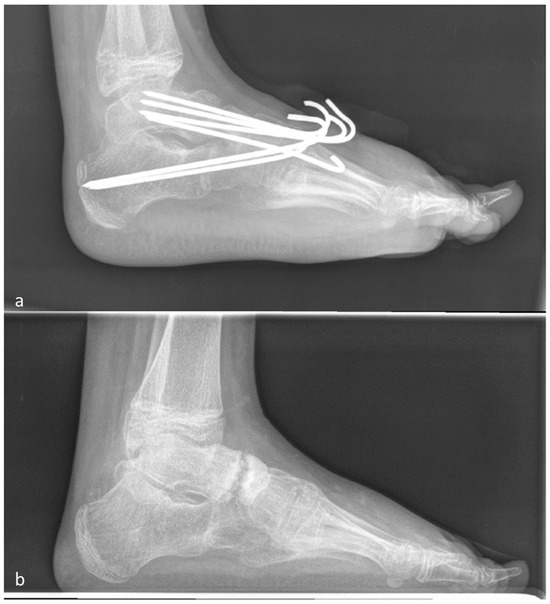

2.1. Operative Procedure

2.4.1. Modified Evans Procedure

2.4.2. Calcaneocuboid Distraction-Fusion

2.4.3. Grice Procedure

2.4.4. Triple Fusion